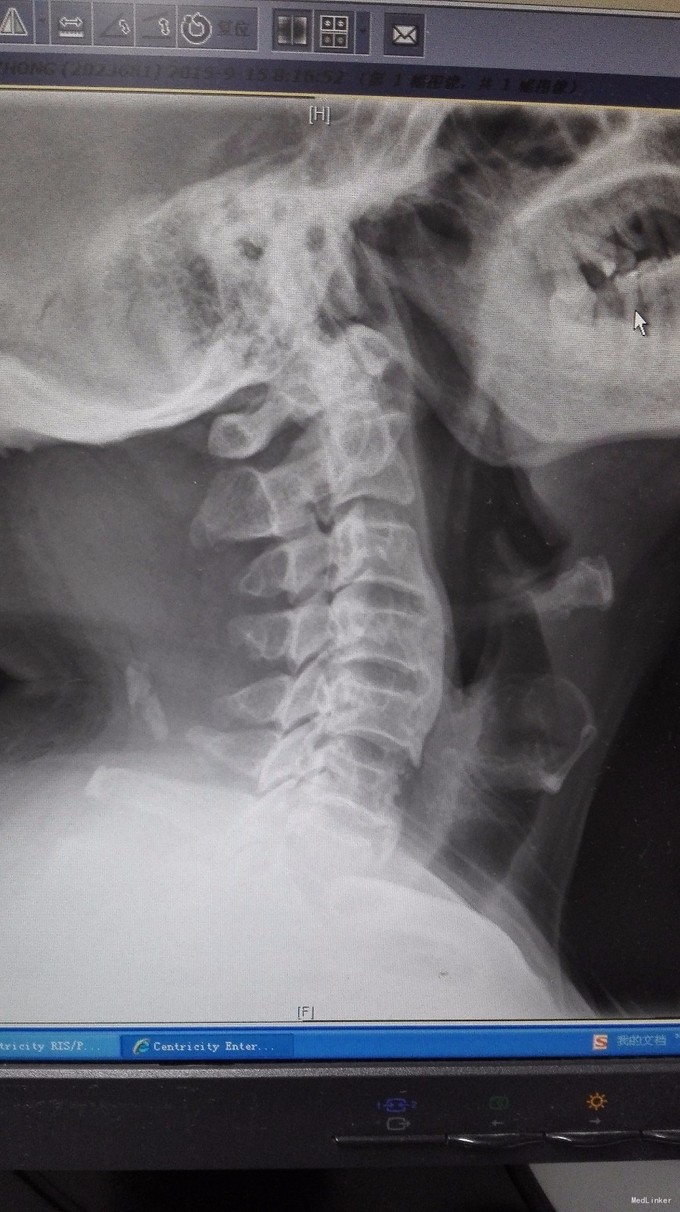

主诉:双手第2、3指尖麻木1年,加重伴双下肢沉重感4月。 病史:1年前出现双手食指、中指指尖麻木,未予以治疗,4月前出现双下肢沉重感,予以腰椎按摩后双下肢症状有所缓解,但双下肢仍有沉重感,右下肢较重,在外院诊治为颈椎病,建议手术治疗,患者拒绝,为求进一步诊治,特来我院就诊,门诊拟混合型颈椎病收入我科住院治疗。

查体:双手麻木感,肱三头肌肌腱反射活跃,左侧髂腰肌4级,臂丛牵拉实验阴性,椎间孔挤压实验阴性。 辅查:CT:C2-7椎间盘突出,继发性椎管狭窄,OPLL,OFL。

诊断:混合型颈椎病(脊髓型+神经根型) 治疗:颈后路3-7单开门椎管扩大成型术(锚定法)